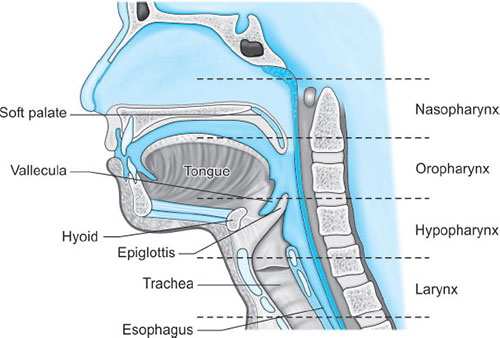

Parts (Fig. 1)

- Nasopharynx: Extends from skull base to soft palate at caudal aspect of C1

- Oropharynx: Extension of nasopharynx to caudal aspect of C3; also involves anterior 1/3 to posterior 2/3rd of tongue

- Layngopharynx (hypopharynx): Merges with esophagus at C6, where the cricopharyngeus encircles the esophagus to form its upper sphincter (similar function of Sellick's maneuver in anesthetized patients).